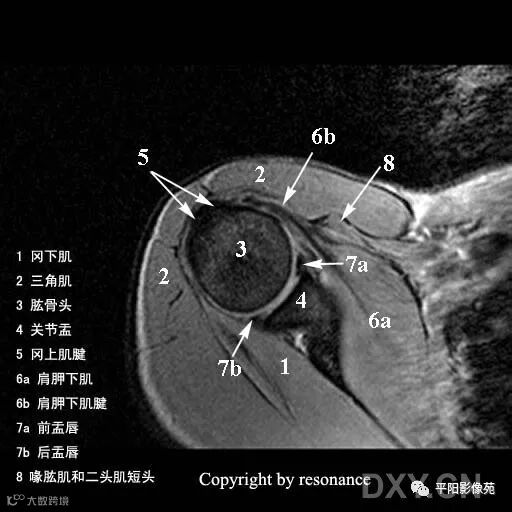

解剖

冈上肌肌腱:斜冠位、轴位显示最佳

止点位于肱骨大结节的上外侧面

冈下肌肌腱:轴位显示佳

止点位于肱骨大结节的后下方

小圆肌肌腱:轴位显示佳

指点位于肱骨大结节更下方,冈下肌肌腱下方

肩胛下肌肌腱:轴位和斜矢状位显示佳

止点位于肱骨小结节的前部